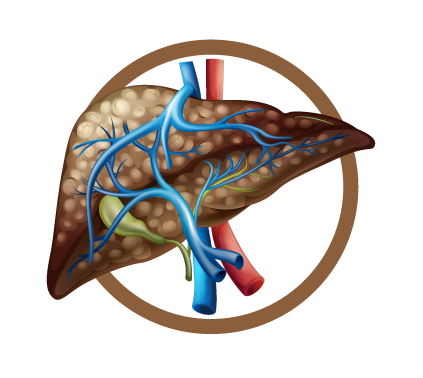

Causas del Hígado graso

Se conocía, por lo general que los hombres que consumían bebidas alcohólicas de forma recurrente sufrían a largo plazo de cirrosis. Sin embargo, en los últimos años es muy común en las citas médicas, ver mujeres con cirrosis por causa del hígado graso.

Incluso, muchas de ellas nunca han consumido bebidas alcohólicas. Hasta los niños menores de 12 años presentan esteatosis hepática.

El Dr. Mike Chang menciona sobre este asunto: “Alguna vez escuché decir a una señora que los niños entre más gorditos están más sanos y entre más flaquitos más enfermo. Es mentira, porque a veces los llenan de colesterol, triglicéridos y su hígado se vuelve grasoso. En esta enfermedad no hay prevalencia de género, ni edad”.

El diagnostica el grado de hígado graso a través de una ecografía, también lo relaciona con los síntomas que presenta el cuerpo. Por ejemplo, si al comer sientes malestares estomacales, diarreas esporádicas, dolor abdominal, picazón al cuerpo o escamas en las manos.

Se asocian los síntomas con los resultados de las enzimas hepáticas. En el cuarto grado el hígado comienza a tener estructuras que se comienzan a dañar, y termina secándose en forma de pasa.

El hígado graso si es reversible, la cirrosis no.